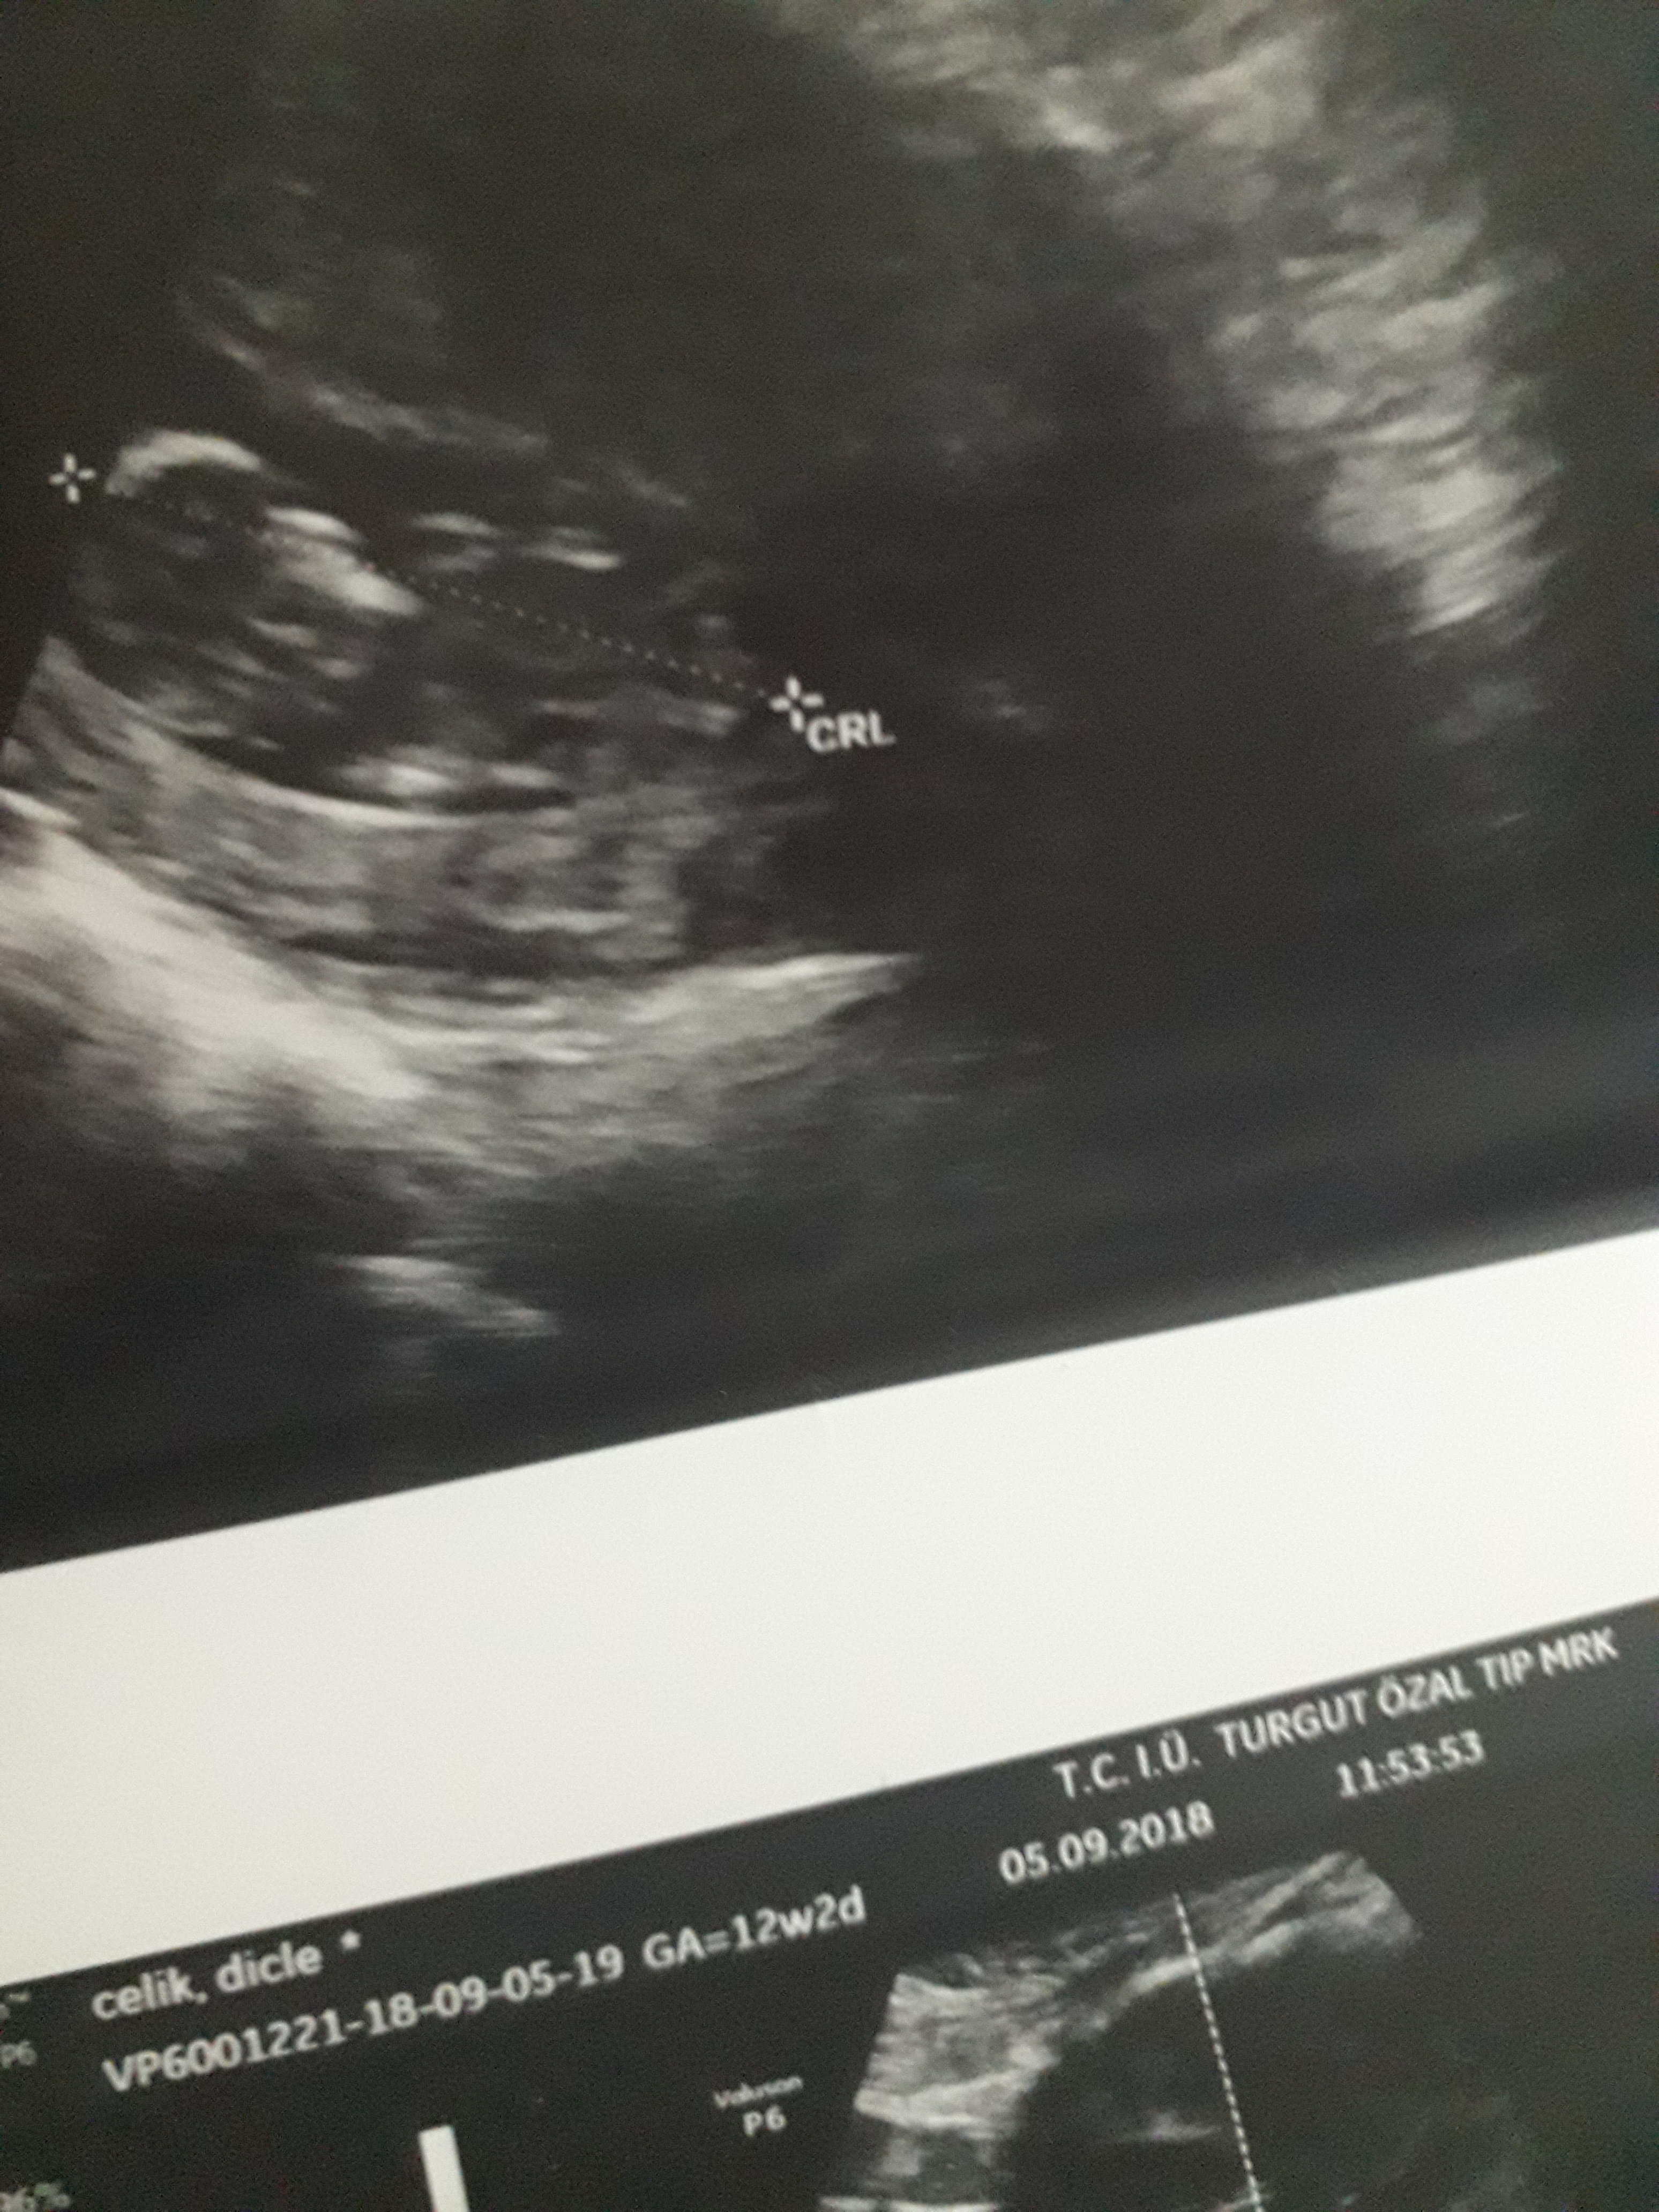

Dun malatyada verildi 12 +4 gunluk lutfen yorumlayin

nub çıkıntısının üzerinde imleç var cinsiyet anlaşılmıyor ilk sayfayı incelemenizi öneriyorum görselin kalitesi konu içinde yer alan görselle aynı olmalıdır.

Görsellerde nub çıkıntısı belli değil . Ultrasonu yapan doktor cinsiyeti hakkında bilgi vermiştir mutlaka ama şunu belirtmeden geçmeyeyim. Bu haftalarda cinsiyet tahmininde yanılma payı çok yüksek 17-19 ve 20 ci haftalarda bebeğin cinsiyetini net olarak öğrenebilirsiniz.